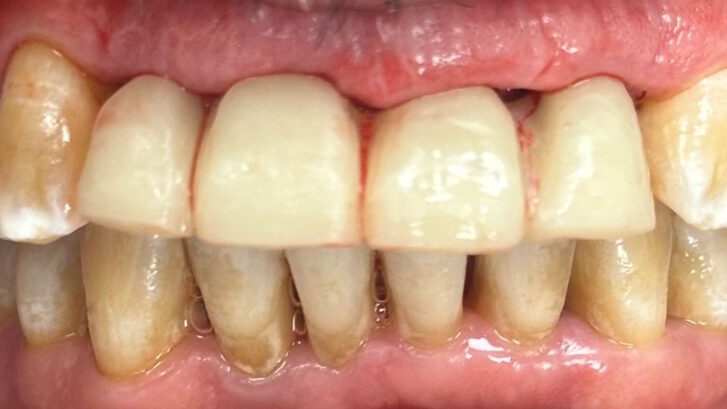

Cuando una persona pasa de esconder su sonrisa a recuperar función, estética y seguridad en apenas unas horas.

Se colocó un provisional de larga duración para controlar la evolución de los tejidos y, como suele ocurrir en este tipo de casos, el paciente refirió molestias mínimas y una mejoría inmediata en función, estética y bienestar.

Es cambiarle la vida a una persona en unas horas.